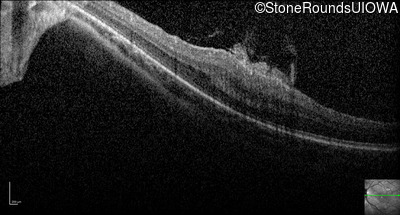

Optical Coherence Tomography - Left - 20/100

Exemplar / OCT Stack